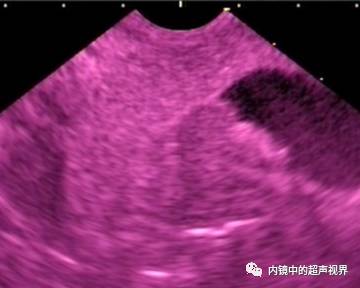

再说伪彩,它把黑白图像处理成黑橙、黑绿、黑蓝、黑粉等图像,一定程度上改变了图像的视感,类似于FICE、iSCAN等后处理光学染色功能,萝卜白菜各有所爱,喜欢哪个直接拿走。